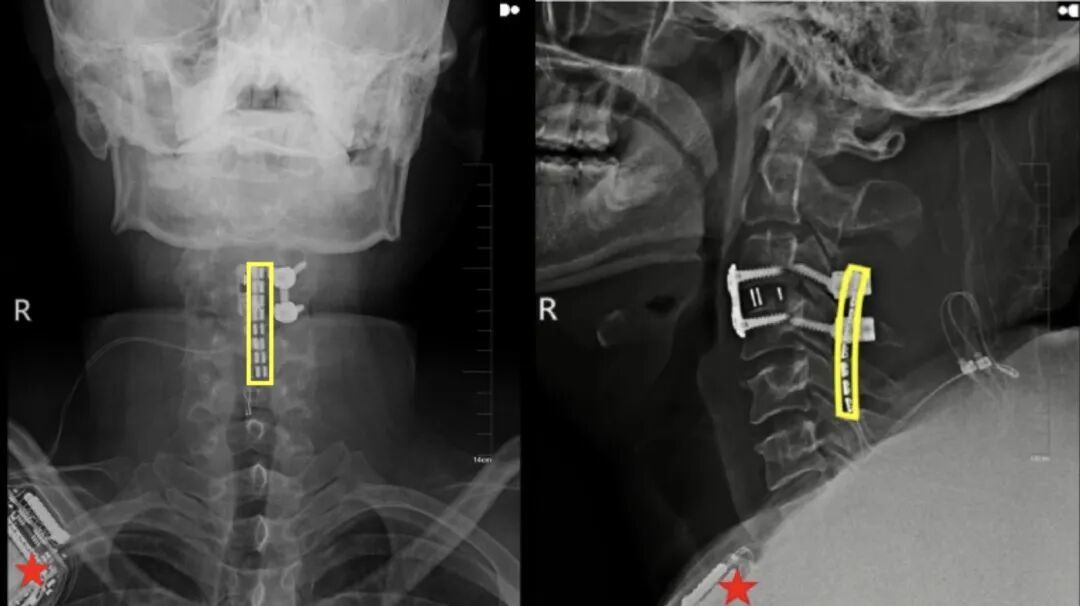

挽救生命是当务之急。刘先生入院后,吉大二院立即启动重伤救治绿色通道,由吴敏飞主刀完成神经减压内固定术。

值得一提的是,手术中,吴敏飞考虑到后续存在着脊髓神经接口植入的可能,同步在颈椎损伤段预留了一个“接口”。

手术非常成功,术后一个月,刘先生的恢复情况良好,生命体征保持稳定。但由于颈椎严重损伤致完全性截瘫,他的脖子以下彻底失去了运动能力和感觉,大小便失禁。